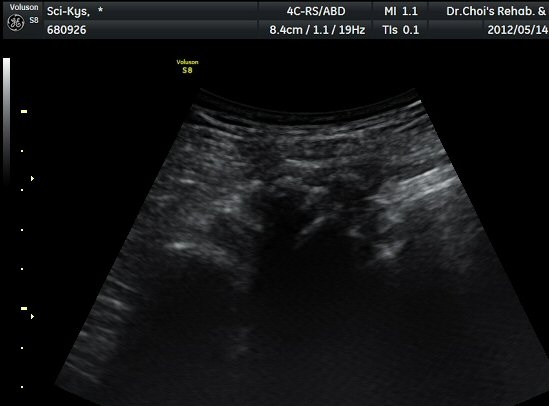

¾ûµ¢ÀÌ Á°ñ¿¡¼­ Á°ñ½Å°æ Ⱦ´Ü¸é°Ë»ç¿¡¼­ ´ëµÐ±Ù°ú quadratus femoris »çÀÌÀÇ ±Ù¸·

°æ°èºÎ¿¡¼­ Á°ñ½Å°æÀÌ °üÂûµÇ´Âµ¥ ³»Ãø Á°ñ°áÀý(ischial tuberosity) ÃøÀ¸·Î Ä¡¿ìÃÄ

ÀÖ´Â °ÍÀ¸·Î ÆÇ´ÜµÈ´Ù(±×¸² 1, 2, 3).

Á¤»óÃø(±×¸² 6, 7)°ú ºñ±³Çϸé Á°ñ½Å°æÀÇ ³»Ãø ÀüÀ§°¡ ¶Ñ·ÈÇÏ´Ù.